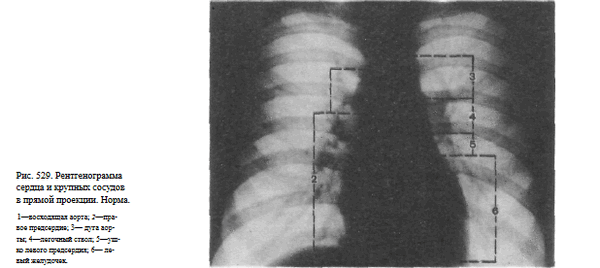

Информативность снимка. На рентгенограмме грудной клетки в прямой проекции у здорового человека сердце расположено таким образом, что — справа от срединной линии. По правому контуру сердечной тени выделяют две дуги: нижняя, более выпуклая, образована правым предсердием; верхняя — восходящей частью аорты. Левый контур сердца состоит из четырех дуг. Нижняя образована передней стенкой левого желудочка; верхняя — дугой аорты в месте ее перехода в нисходящую.

Под дугой аорты располагается легочный ствол. Между легочным стволом и дугой левого желудочка — ушко левого предсердия (рис. 529).

Рентгенограмма органов грудной клетки в прямой проекции. Обозначения: ЛЖ - левый желудочек, ПП - правое предсердие, ЛП - ушко левого предсердия, ЛС -легочной ствол, ДАо - дуга аорты, ВАо - восходящий отдел аорты.

В прямой передней проекции сердце и крупные сосуды занимают положение в средостении таким образом, что 2/3 сердечной тени находится слева, 1/3 - справа. Вдоль правого контура сердечно-сосудистой тени образуются две дуги. Верхняя дуга образована верхней полой веной (в некоторых случаях восходящей аортой). Нижняя - правым предсердием. По длине они соотносятся, как 1/1. Место схождения этих дуг называется правым атриовазальным углом. Расстояние от срединной линии до наружного контура первой дуги в этой проекции 3-4 см. Нижняя дуга правого контура в прямой проекции находится от правого края контура грудных позвонков на расстоянии от 1 до 2,5 см.

Вдоль левого контура сердечно-сосудистой тени расположены четыре дуги. Последовательно сверху вниз их образуют: дуга и начальный отдел нисходящей аорты, легочной ствол, ушко левого предсердия, левый желудочек.